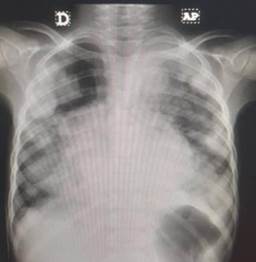

Se realiza estudio radiológico de tórax, apreciándose lesiones radiopacas, redondeadas, múltiples en región mediastínica y periférica del tórax. Es evaluada por el servicio de Neumonología considerándose patología neoplásica pulmonar, por lo que se solicita ecografía y Tomografía Axial Computarizada (TAC) de tórax.

Imagen 4.

Radiografía de tórax a los 6 años de edad